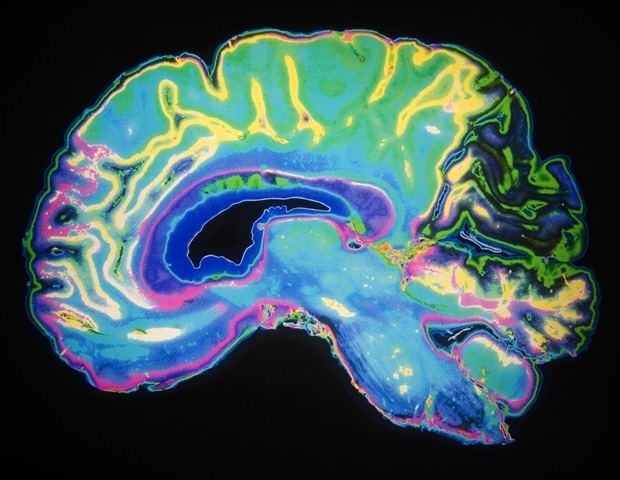

Новое исследование экспертов из Университета штата Джорджия достигло давней цели в области нейробиологии: показать, как мельчайшие компоненты мозга создают системы, формирующие мышление, эмоции и поведение.

Исследование, опубликованное в журнале Nature Communications, может изменить представление ученых о когнитивных способностях и старении, а также таких расстройствах психического здоровья, как депрессия и шизофрения.

Объединив сканирование мозга с генетическими данными и молекулярной визуализацией, исследователи обнаружили подробную биологическую карту, связывающую различные уровни мозга и раскрывающую долгожданный мост между микро- и макроуровнями организации мозга.